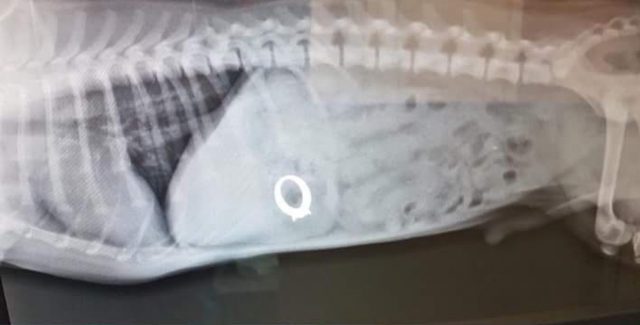

Fue al pasar la máquina junto a su mascota cuando el dispositivo sonó. La mujer supo entonces que su perro, un jack russell de nombre Bertie, se había tragado el anillo. A partir de ahí decidió llevarle al veterinario donde una radiografía reveló la presencia de la joya en el interior del can.

Bertie tuvo que ser intervenida para extraer el anillo de sus intestinos.